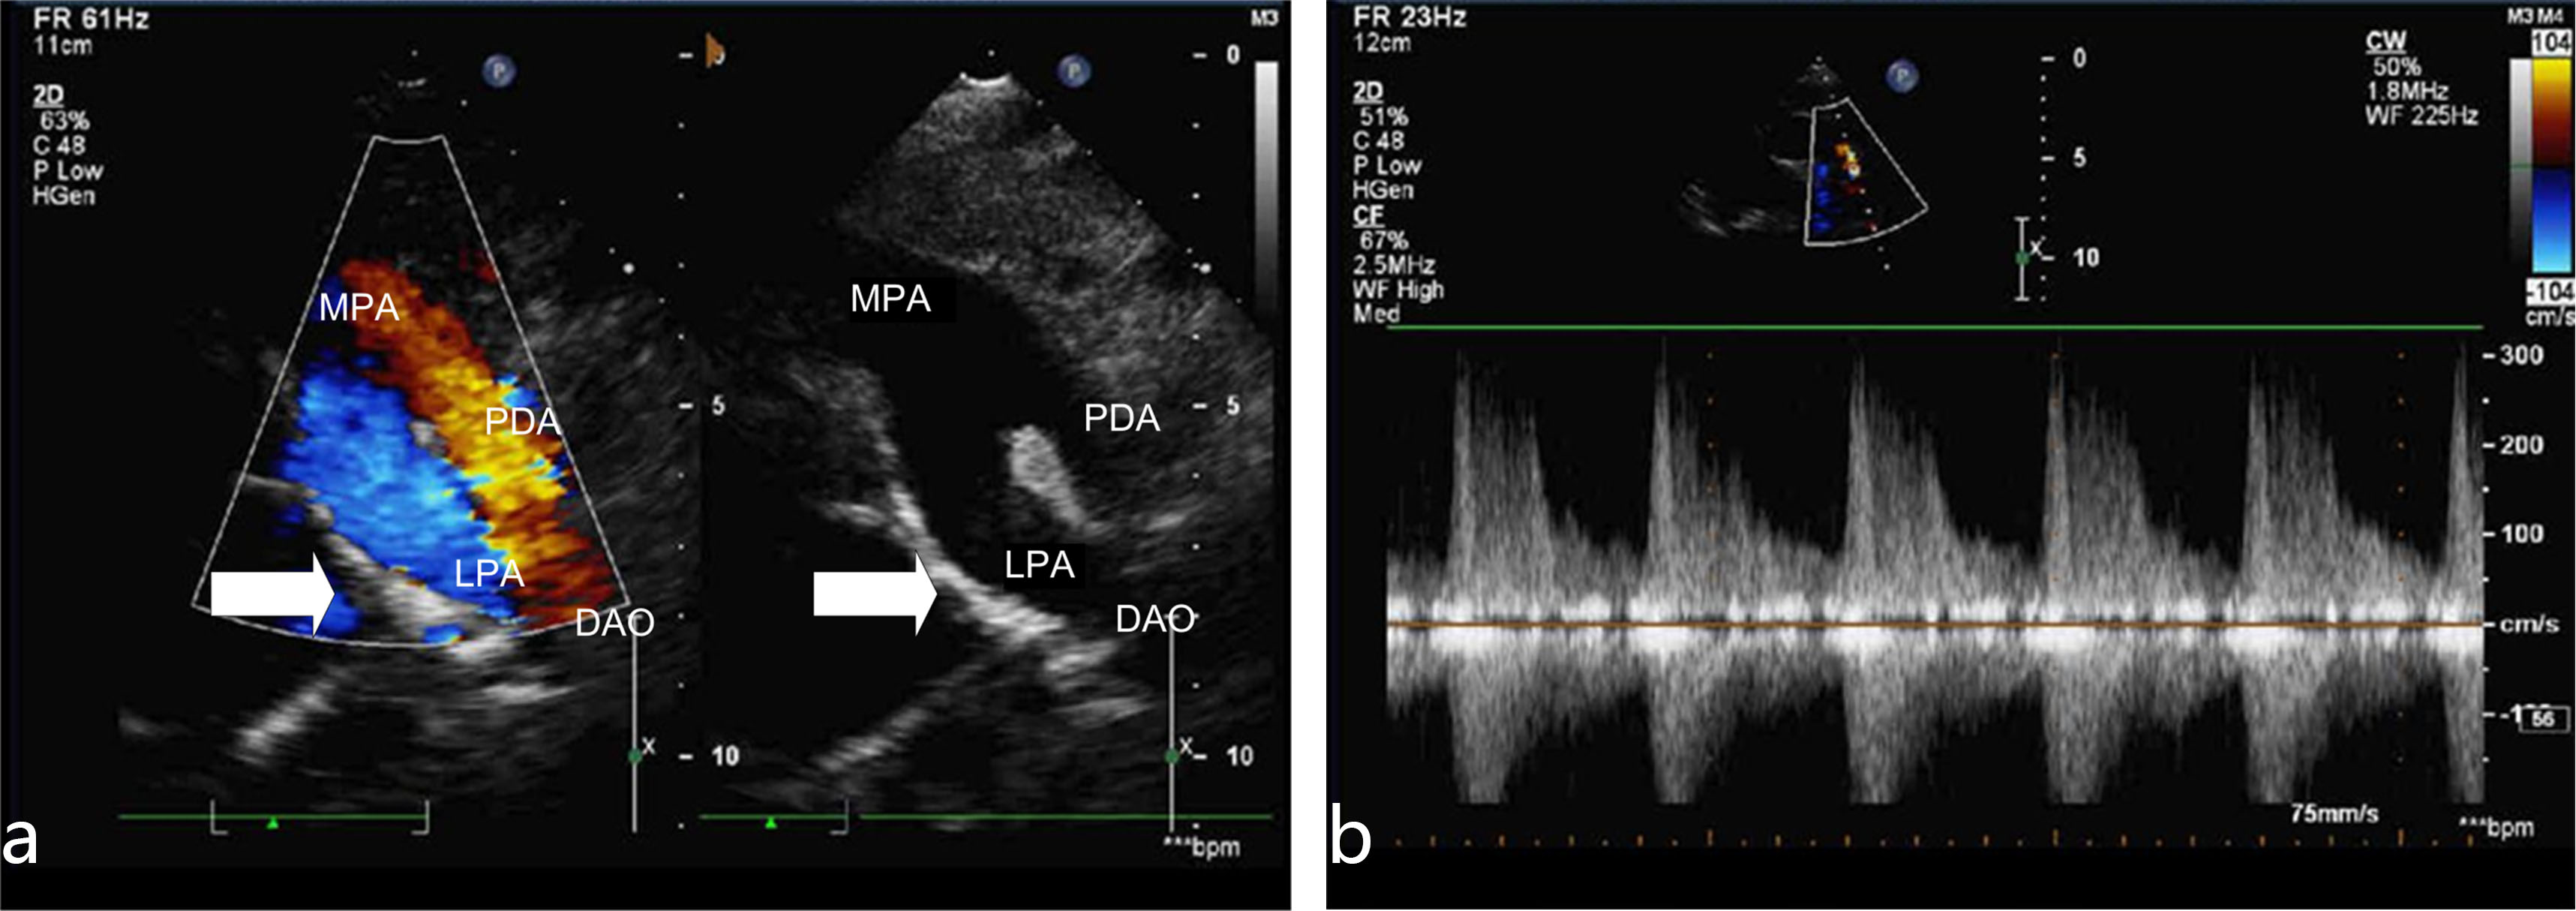

Typical case analysis: The absence of right pulmonary artery with patent ductus arteriosus is shown in Fig. 1 (hypertension group). There is no right pulmonary artery structure in the trunk of pulmonary artery. There is a pipeline between the root of left pulmonary artery and descending aorta (PDA).

Fig. 1.Typical echocardiography of right pulmonary artery absence. (a) Short axis view of great vessels (Color Doppler and 2D image). In this view there is not right pulmonary artery structure from the main pulmonary artery (arrow). PDA, patent ductus arteriosus; MPA, main pulmonary artery; LPA, left pulmonary artery; DAO, descending aorta. (b) Continuous Doppler detected pulmonary artery regurgitation. This case showed mild pulmonary artery regurgitation, estimate the mean pulmonary artery pressure, indicating that the patient has pulmonary hypertension.

In addition, the reasons of ultrasound misdiagnosis in UAPA is mainly due to insufficient caution of this disease during scanning. This may be due to insufficient understanding of the disease or the patient’s image is unclear due to lung disease. If it was found that the pulmonary artery was not clearly displayed in the examination, cardiologists or sonographers should pay attention to scanning the high level short-axis view of the great vessels. Use color Doppler to detect pulmonary artery branch and the situation of the left and right pulmonary artery. According our experience, there were two situation were most easily misdiagnosed: (1) For the left pulmonary artery absence patient, the ductus arteriosus is often misdiagnosed as a pulmonary artery branch (Fig. 1). This may be due to insufficient knowledge of the disease or the operating doctor’s inadequate scanning of the branches of the pulmonary artery. (2) Tetralogy of Fallot (TOF) patients combined with the absence of pulmonary arteries are easily missed also (Fig. 4), the misdiagnosis rate was as high as 77% (7/9), the reason was considered as following: TOF patient’s pulmonary artery branches were usually very thin, which were difficult to detect by 2D echocardiography, and pulmonary stenosis induced blood flow turbulence, which affected pulmonary branch color Doppler imaging.